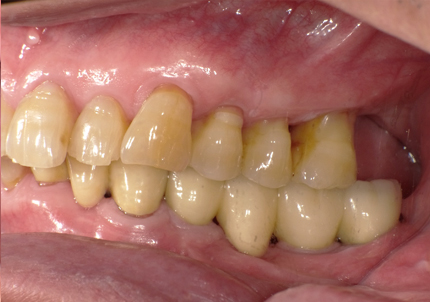

↑ 2025年9月9日

治療後は経過良好